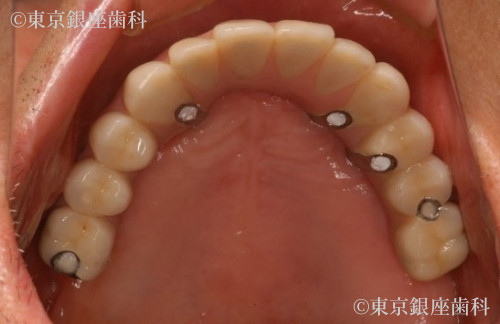

After

ブレードインプラントが下顎管に近接しているので、インプラント除去による下顎の知覚麻痺が生じるリスクを術前のCTの分析で診査し、リスクを避けました。また骨造成は行わず、既存骨(ご本人様の骨)イへのンプラント埋入を行いました。上顎は5本のインプラント、下顎は4本のインプラントを支えとした、上下顎への全顎的な人工歯を装着することで口腔機能の回復が得られた症例となりました。患者様にとても満足の得られることができた症例です